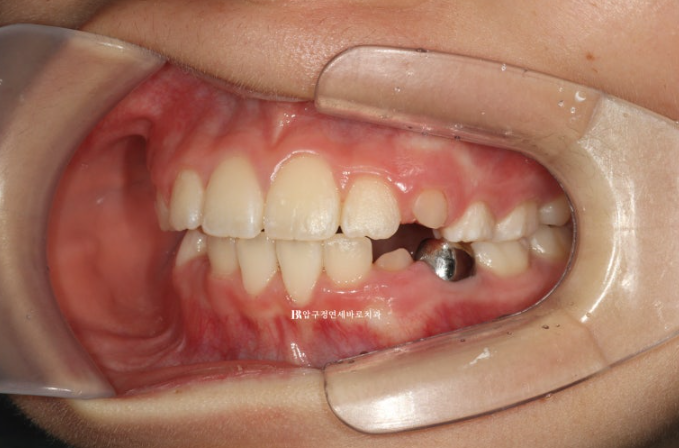

22.11.23

병원에 처음 온 날 모습입니다.

문제점을 나열해보자면

과개교합 (앞니가 깊게 물림)

덧니 (삐뚤빼뚤)

후속 영구치가 나올 공간 부족

그리고 아이의 개인적인 문제점은 당장 한달뒤에 외국에 나가 6개월 후 귀국

이런상황들에 맞춰 치료계획을 만들었습니다.